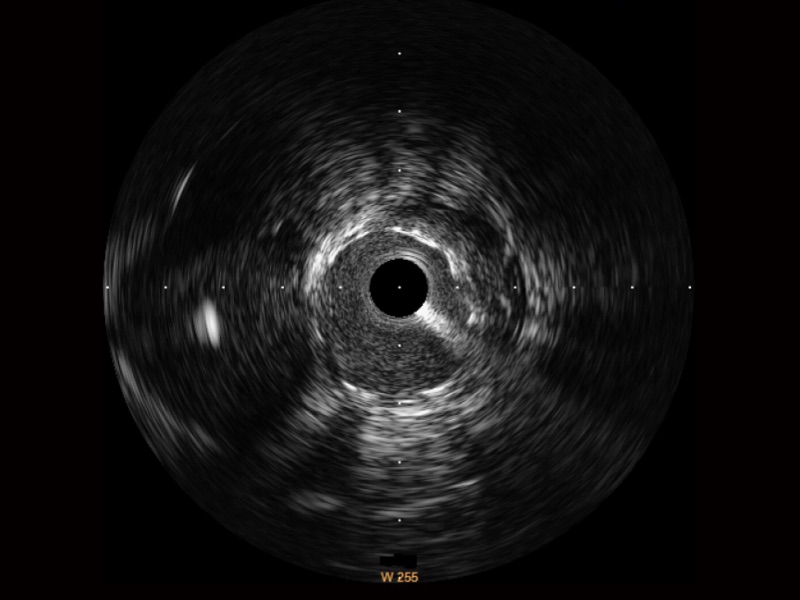

• 百老汇电子游戏官网宽频IVUS图像

对比传统IVUS导管成像,百老汇电子游戏官网宽频IVUS图像的近场支架梁显影更细腻,远场中膜外血管仍清晰可辨,兼顾远中近,兼顾分辨力与穿透深度